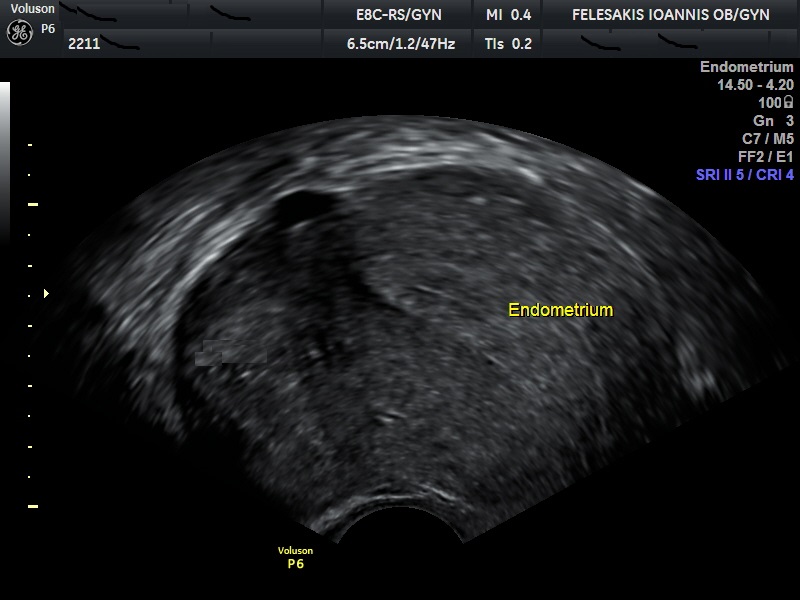

Τα συνηθέστερα συμπτώματα των γυναικών είναι η δυσμηνόρροια, η μηνορραγία και ο πόνος κατά την επαφή (δυσπαρεύνια). Σημαντικό είναι να τονιστεί, ότι η αδενομύωση δεν οδηγείται σε εξαλλαγή σε καρκίνο. Η διάγνωση της αδενομύωσης είναι δύσκολη, καθώς η υπερηχογραφική της εικόνα, πολλές φορές ομοιάζει με αυτή των ινομυωμάτων. Τη λύση έχει δώσει η Μαγνητική Τομογραφία (MRI) η οποία και βοηθάει στη διαφορική διάγνωση της υποκείμενης πάθησης.